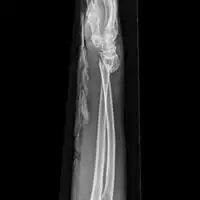

![]() | |

| Midshaft fracture of the radius and ulna | |